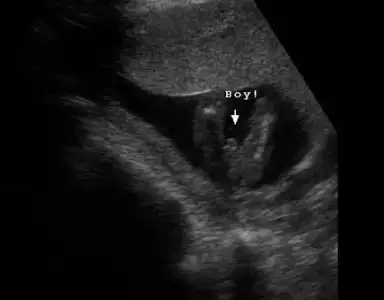

dr soylemeden siz gorun genital nub teorisi ( bebegin cinsiyeti)

Ilk resim aynı kız bebek bacak arası. Ikincisi tam erkek gibi değil ama kız gibi değil. Fakat 16 haftalık erkek bebek ilk resimdeki pozisyonda aşağı eklediğim resimde gibi görünüyor. Yani internette hep öyle.